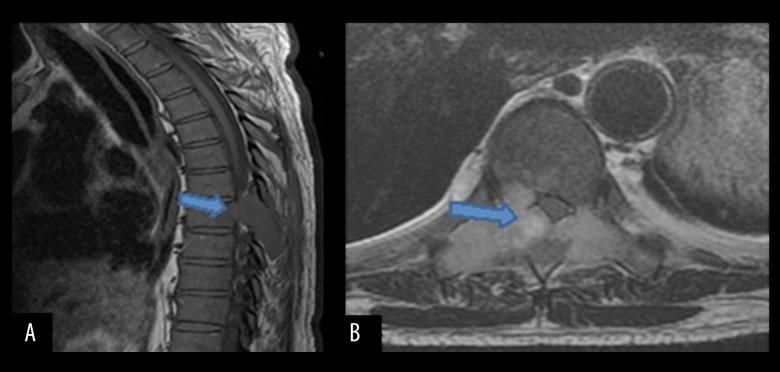

BACKGROUND Sarcomatoid carcinoma is a rare, aggressive, malignant cancer composed of sarcoma and sarcoma-like components, and can occur in different organs such as the thyroid gland, bone, skin, breast, pancreas, liver, urinary tract, and lung. Pulmonary sarcomatoid carcinoma accounts for only a small percentage of lung cancers and has histological variants that include pleomorphic carcinoma, giant cell carcinoma, spindle cell carcinoma, carcinosarcoma, and pulmonary blastoma. CASE REPORT Here, we present a case of sarcomatoid carcinoma in a 63-year-old HIV-positive Hispanic male who presented with back pain, dry cough, and weight loss. A CT scan of his chest showed an ovoid mass in the lower lobe of the left lung, and an MRI of the spine showed a left lateral paraspinal soft tissue mass causing central canal stenosis and mild cord compression. The patient underwent laminectomy and resection of the spinal mass. A transthoracic needle biopsy of the lung and spinal masses had similar histopathology, and were indicative of sarcomatoid carcinoma. CONCLUSIONS We report a rare case of sarcomatoid carcinoma involving both the lung and spinal cord in the same patient. Sarcomatoid carcinomas of the lung have poor prognosis and are aggressive cancers. Moreover, our case also had the co-occurrence of HIV and sarcomatoid carcinoma.

肉瘤样癌是一种罕见的侵袭性恶性肿瘤,由肉瘤和肉瘤样成分组成,可发生于不同器官,如甲状腺、骨骼、皮肤、乳腺、胰腺、肝脏、泌尿道和肺部。肺肉瘤样癌仅占肺癌的一小部分,具有多种组织学变异型,包括多形性癌、巨细胞癌、梭形细胞癌、癌肉瘤和肺母细胞瘤。病例报告:在此,我们报告一例63岁的HIV阳性西班牙裔男性肉瘤样癌患者,该患者出现背痛、干咳和体重减轻症状。胸部CT扫描显示左肺下叶有一个椭圆形肿块,脊柱MRI显示左侧椎旁软组织肿块,导致中央管狭窄和轻度脊髓受压。患者接受了椎板切除术和脊柱肿块切除术。对肺部和脊柱肿块进行的经胸针吸活检具有相似的组织病理学表现,提示为肉瘤样癌。结论:我们报告了一例罕见的同一患者同时发生肺和脊髓肉瘤样癌的病例。肺肉瘤样癌预后较差,是侵袭性癌症。此外,我们的病例还同时存在HIV和肉瘤样癌。